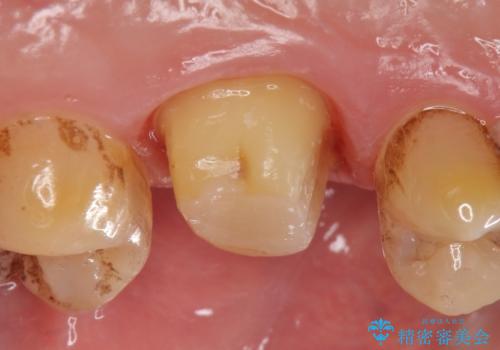

診査の結果、左上6が失活(歯の神経が死んでいる状態)しており根尖病変を認めたため、根管治療を行いました。

根尖病変の縮小及び症状の消失を確認後、オールセラミッククラウンによる補綴を行いました。

今回用いたオールセラミッククラウンはジルコニアフレームという白い素材の上にセラミックを盛っているため、審美性が非常に高いのが特徴です。

また、ジルコニアは人工ダイヤモンドの材料にも使われているほど高い強度を持っており、そのためオールセラミッククラウンは審美性だけでなく、奥歯やブリッジの補綴も可能とするクラウンです。